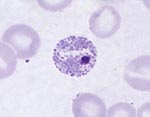

Paracoccidioides brasiliensis CNH

|

[ Opisthokonta | Fungi | Dikarya | . . .

. . . | Onygenales | Onygenales incertae sedis | Paracoccidioides ]

|

Paracoccidioides brasiliensis Pb01

|

[ Opisthokonta | Fungi | Dikarya | . . .

. . . | Onygenales incertae sedis | Paracoccidioides | Paracoccidioides lutzii ]

Picture Source

Picture Source

|

| Taxonomy: | Eukaryota | Opisthokonta | Fungi | Dikarya | Ascomycota | saccharomyceta | Pezizomycotina | leotiomyceta | Eurotiomycetes | Eurotiomycetidae | Onygenales | Onygenales incertae sedis | Paracoccidioides | Paracoccidioides lutzii |

| Synonym: | Paracoccidioides sp. 'lutzii' Pb01, Loboa loboi, Aleurisma brasiliensis (obsolete), Blastomyces brasiliensis (obsolete), Coccidioides brasiliensis (obsolete), Coccidioides histosporocellularis (obsolete), Lutziomyces histosporocellularis (obsolete), Monilia brasiliensis (obsolete), Mycoderma brasiliensis (obsolete), Mycoderma histosporocellularis (obsolete), Zymonema brasiliense (obsolete) |

| Comment: | Paracoccidioides brasiliensisis dimorphic and the causative agent for paracoccidioidomycosis, a chronic granulomatous disease of mucous membranes, skin, and pulmonary system. In contrast to the other yeasts, particularly Blastomyces, Paracoccidioides has multiple buds, a thin cell wall, and a narrow base. |

|

|

|

Go to NCBI Taxonomy (502779) |

|

|

|  |

Encyclopedia of life |

|

|  |

Wikipedia |

| Publication: |

Desjardins CA, Champion MD, Holder JW et. al.

( 2011)

PLoS Genet 7, e1002345.

|